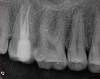

This report illustrates a rare case of a geminated maxillary right second molar tooth using CBCT in a 23-year-old man with severe pain. Nonsurgical endodontic treatment was performed, which gave rise to an asymptomatic tooth at the 12-month follow-up.